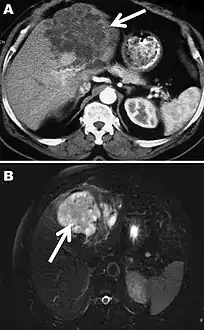

Computed tomography (A) and magnetic resonance (B) images of the liver of a 72-year-old man from French Guiana with polycystic echinococcosis affecting the left side of the liver. White arrows indicate the multicystic liver lesion.